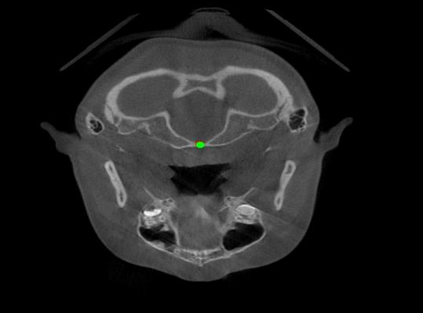

Detecting 3D landmarks on cone-beam computed tomography (CBCT) is crucial to assessing and quantifying the anatomical abnormalities in 3D cephalometric analysis. However, the current methods are time-consuming and suffer from large biases in landmark localization, leading to unreliable diagnosis results. In this work, we propose a novel Structure-Aware Long Short-Term Memory framework (SA-LSTM) for efficient and accurate 3D landmark detection. To reduce the computational burden, SA-LSTM is designed in two stages. It first locates the coarse landmarks via heatmap regression on a down-sampled CBCT volume and then progressively refines landmarks by attentive offset regression using multi-resolution cropped patches. To boost accuracy, SA-LSTM captures global-local dependence among the cropping patches via self-attention. Specifically, a novel graph attention module implicitly encodes the landmark's global structure to rationalize the predicted position. Moreover, a novel attention-gated module recursively filters irrelevant local features and maintains high-confident local predictions for aggregating the final result. Experiments conducted on an in-house dataset and a public dataset show that our method outperforms state-of-the-art methods, achieving 1.64 mm and 2.37 mm average errors, respectively. Furthermore, our method is very efficient, taking only 0.5 seconds for inferring the whole CBCT volume of resolution 768$\times$768$\times$576.